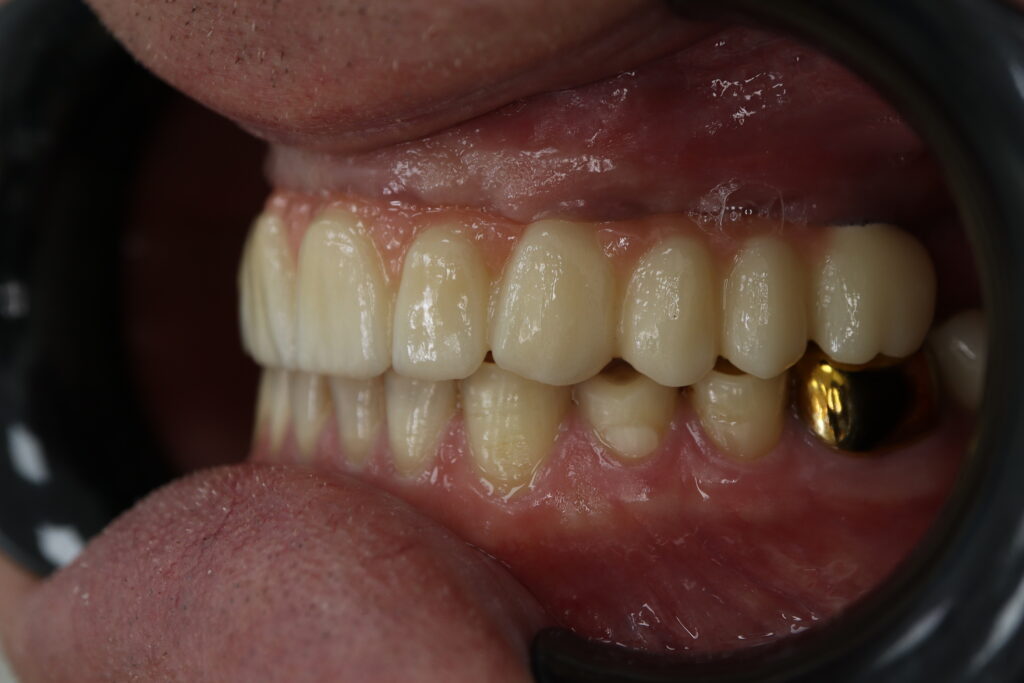

Спустя 27 дней был зафиксирован протез с опопрой на дентальные имплантаты из диоксида циркония с каркасом из титана.

Также на нижнюю челюсть был изготовлен мостовидный протез из 4х коронок (цирконий) с опорой на 3 индивидуальных абатмента с одной стороны и 1 коронка на иплантат с другой.

Пациенту были установлены 6 имплантатов Megagen AnyOne по системе All-on-6 на верхней челюсти и 4 имплантата на нижней по классической двухэтапной методике.